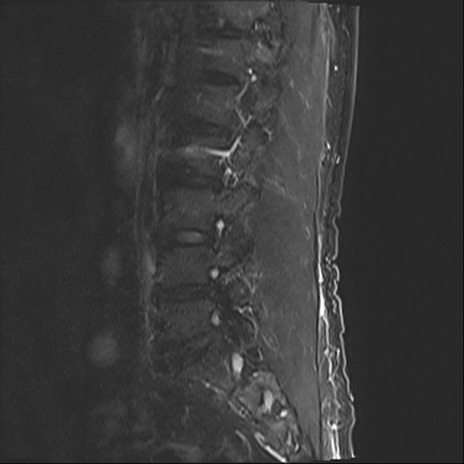

【整形】TIPS症例2 腰椎MRI STIR(矢状断像)

【症例】70歳代男性

【主訴】左下肢痛

【現病歴】2週間前くらいから腰痛、左下肢痛あり。左臀部から大腿、下腿外側のしびれが常時ある。歩行とともに同部位の痛みあり。

【身体所見】Lasegue70-/60+、Bragard-/±、PTR ±/±、ATR -/-、IP 5/5、TA 5/4、TS 5/5、EHL 右第1足趾なし/3、FHL 5/5、hypersthesia(-)、足背動脈触知良好

異常所見と診断は?